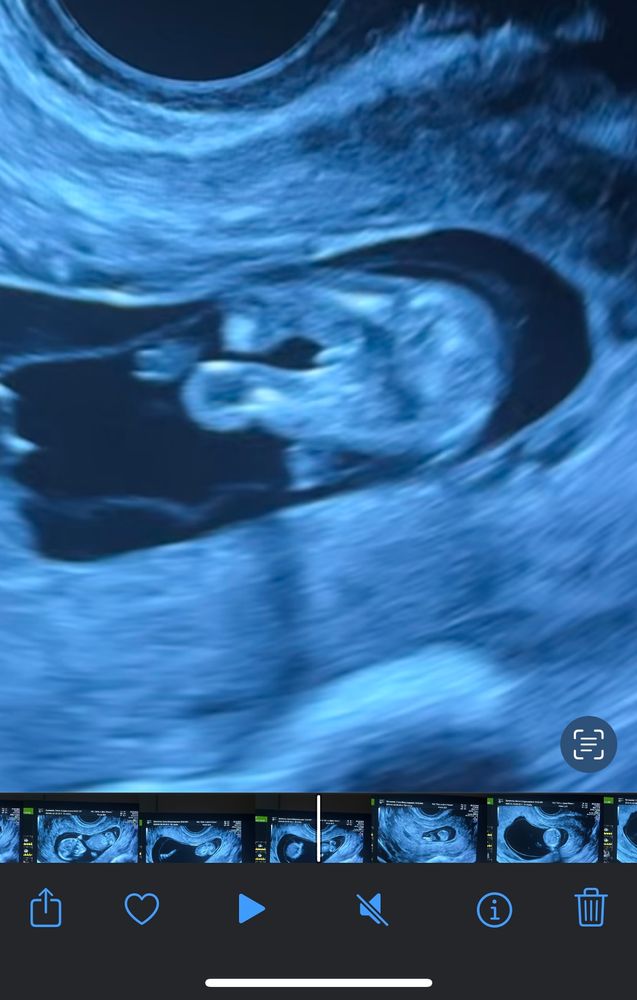

Пол малышаДевочки, давайте погадаем вместе это писька или пуповинка?)

С этого ракурса на этой неделе не понять. У всех есть что-то между ножек, это половой бугорок. Нет еще половых губ и половой щели, как и мошонки, так что подождите

Больше на пуповину похоже

Вероятнее всего девчуля

У мальчишек прям торчком

Но ракурс такой себе